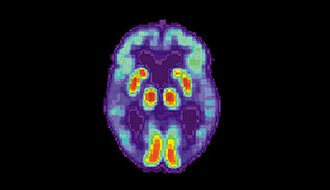

以影像技術,指出血清膽固醇與腦中β-amyloid沈澱的關聯性。Using new technic to investigate the associations between serum cholesterol levels and cerebral amyl [‧‧‧‧‧]